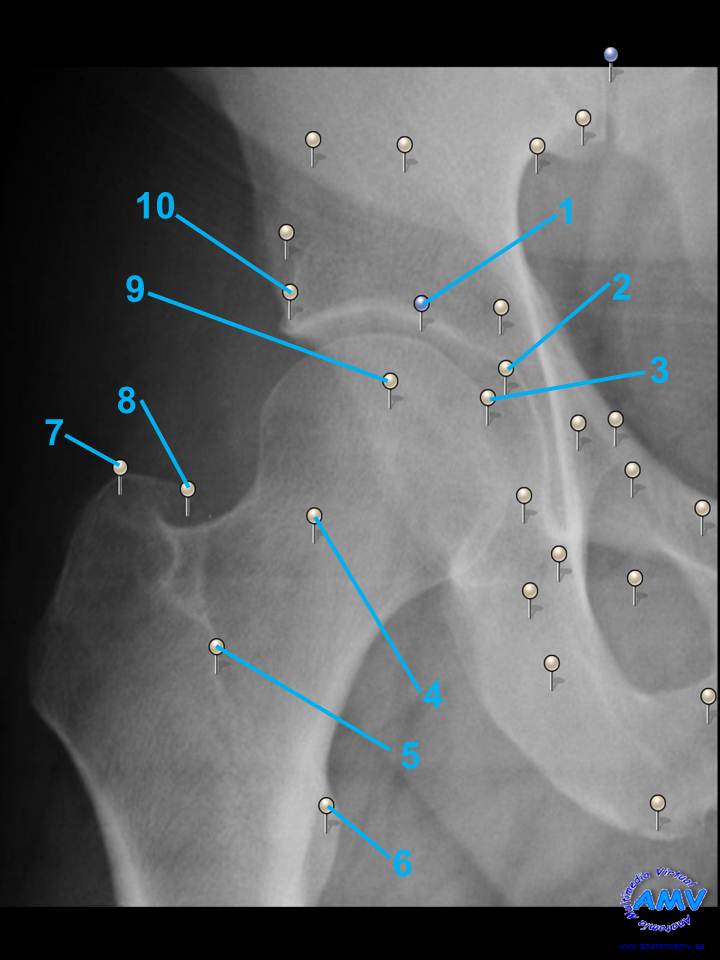

Radiografía Articulación de la Cadera

rx_mi_03.jpgIndique que estructura se señala con el número correspondiente:

El nº 1 señala .

El nº 2 señala .

El nº 3 señala .

El nº 4 señala .

El nº 5 señala .

El nº 6 señala .

El nº 7 señala .

El nº 8 señala .

El nº 9 señala .

El nº 10 señala .